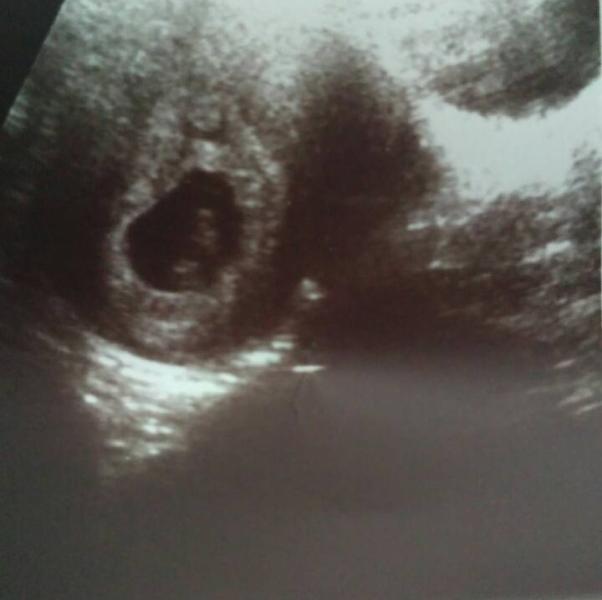

у меня тоже саме фото😀 вчера была на узи..сказали яйцо не ровное😯

смотрю на это фото и мне кажется что я уже вижу головку, глазки, ручки😃😃😃

тьфу тьфу врач узист сказала что все хорошо